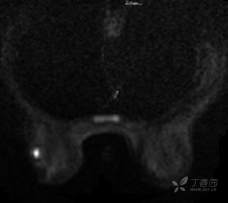

DWI

乳腺MR:左乳外上象限见T2WI高信号肿块影,大小约12mm×10mm×13mm,肿块为卵圆形,边缘模糊不规则;内部强化略不均匀;TIC曲线初始相呈快速强化,延迟期呈平台型;DWI呈高信号,ADC值为 0.000698 mm2/s。

因肿块边缘不规则,内部强化不均匀, TIC曲线初始相呈快速强化,延迟期呈平台型;DWI呈高信号,ADC值较低,考虑左乳外上象限肿块恶性不除外,BIRADS 4类。

病灶DWI成像呈等信号